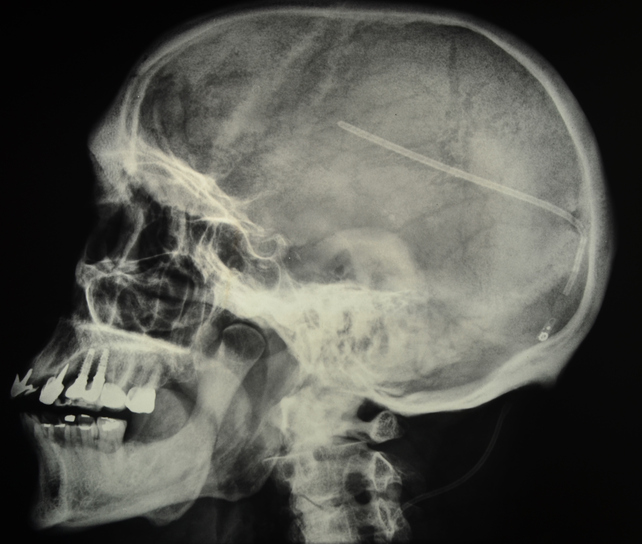

Ventriculostomy, or shunt, is a neurosurgical procedure that involves creating a hole within a cerebral ventricle for drainage. It is most commonly performed on those with hydrocephalus. It is done by surgically penetrating the skull, dura mater, and brain such that the ventricular system ventricle of the brain is accessed.